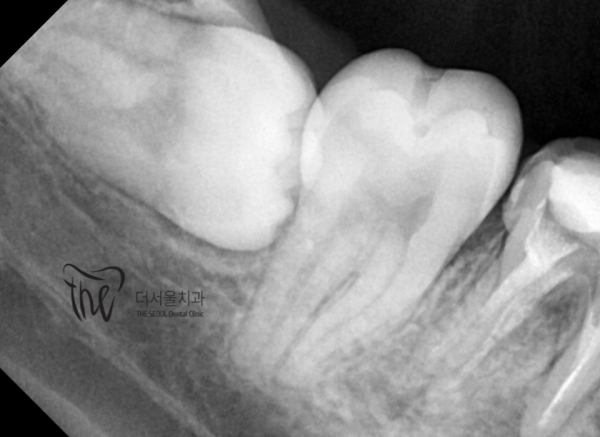

저희 모란역치과 더서울치과는 디지털치과로서 환자분들의 사랑니발치를

하기전, CT촬영, 엑스레이촬영 등을 통해 사랑니와 주변 조직의 관계를 정확히

파악하여 발치계획을 세운 후, 안전하고 정확하게 발치를 진행하게됩니다.

Our Moran Station Dental Clinic, The Seoul Dental Clinic, is a digital dental clinic that helps patients get their wisdom teeth removed

Before doing it, CT scans, x-rays, etc., the relationship between wisdom teeth and surrounding tissues was accurately determined

After grasping and making a extraction plan, the extraction will be carried out safely and accurately.